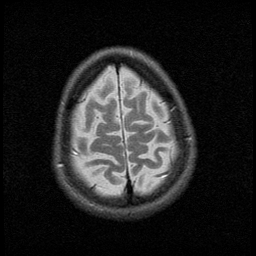

Huntington's Chorea, MR -- Slice #18

[Home][Help][Clinical] Slice 18